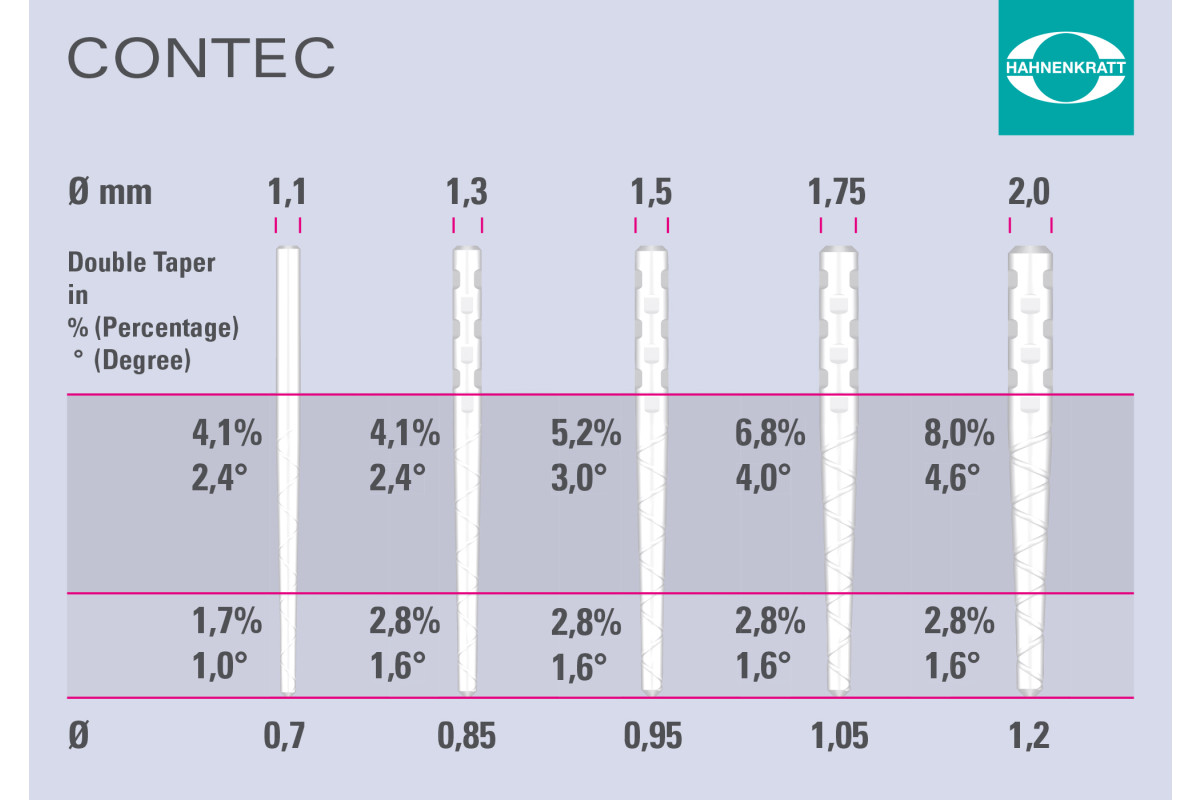

ContecPRO – Posts & Drills

Drills